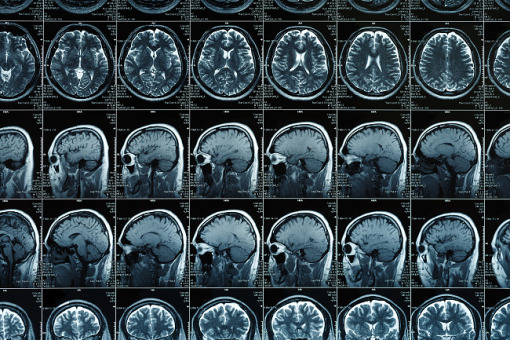

Jedną z metod terapeutycznych depresji jest przezczaszkowa stymulacja magnetyczna mózgu (TMS). Jednak jej skuteczność znacznie różni się w zależności od osoby. Badacze przeanalizowali skany MRI mózgów ponad 1600 pacjentów z depresją i ponad 1300 osób zdrowych. W ten sposób dokładnie opisali spowodowane chorobą zmiany w obszarze zwanym podkolankową przednią korą obręczy (sgACC), którego uszkodzenia często towarzyszą depresji.

Jednym z najważniejszych odkryć było to, że nieprawidłowa łączność między tym regionem a lewą grzbietowo-boczną korą przedczołową (DLPFC) wpływa zarówno na anatomiczne położenie optymalnych punktów stymulacji TMS, jak i na wyniki leczenia pacjentów. Naukowcy zaproponowali nowy algorytm, który łączy statystyczne mapy mózgu ze spersonalizowanymi danymi.